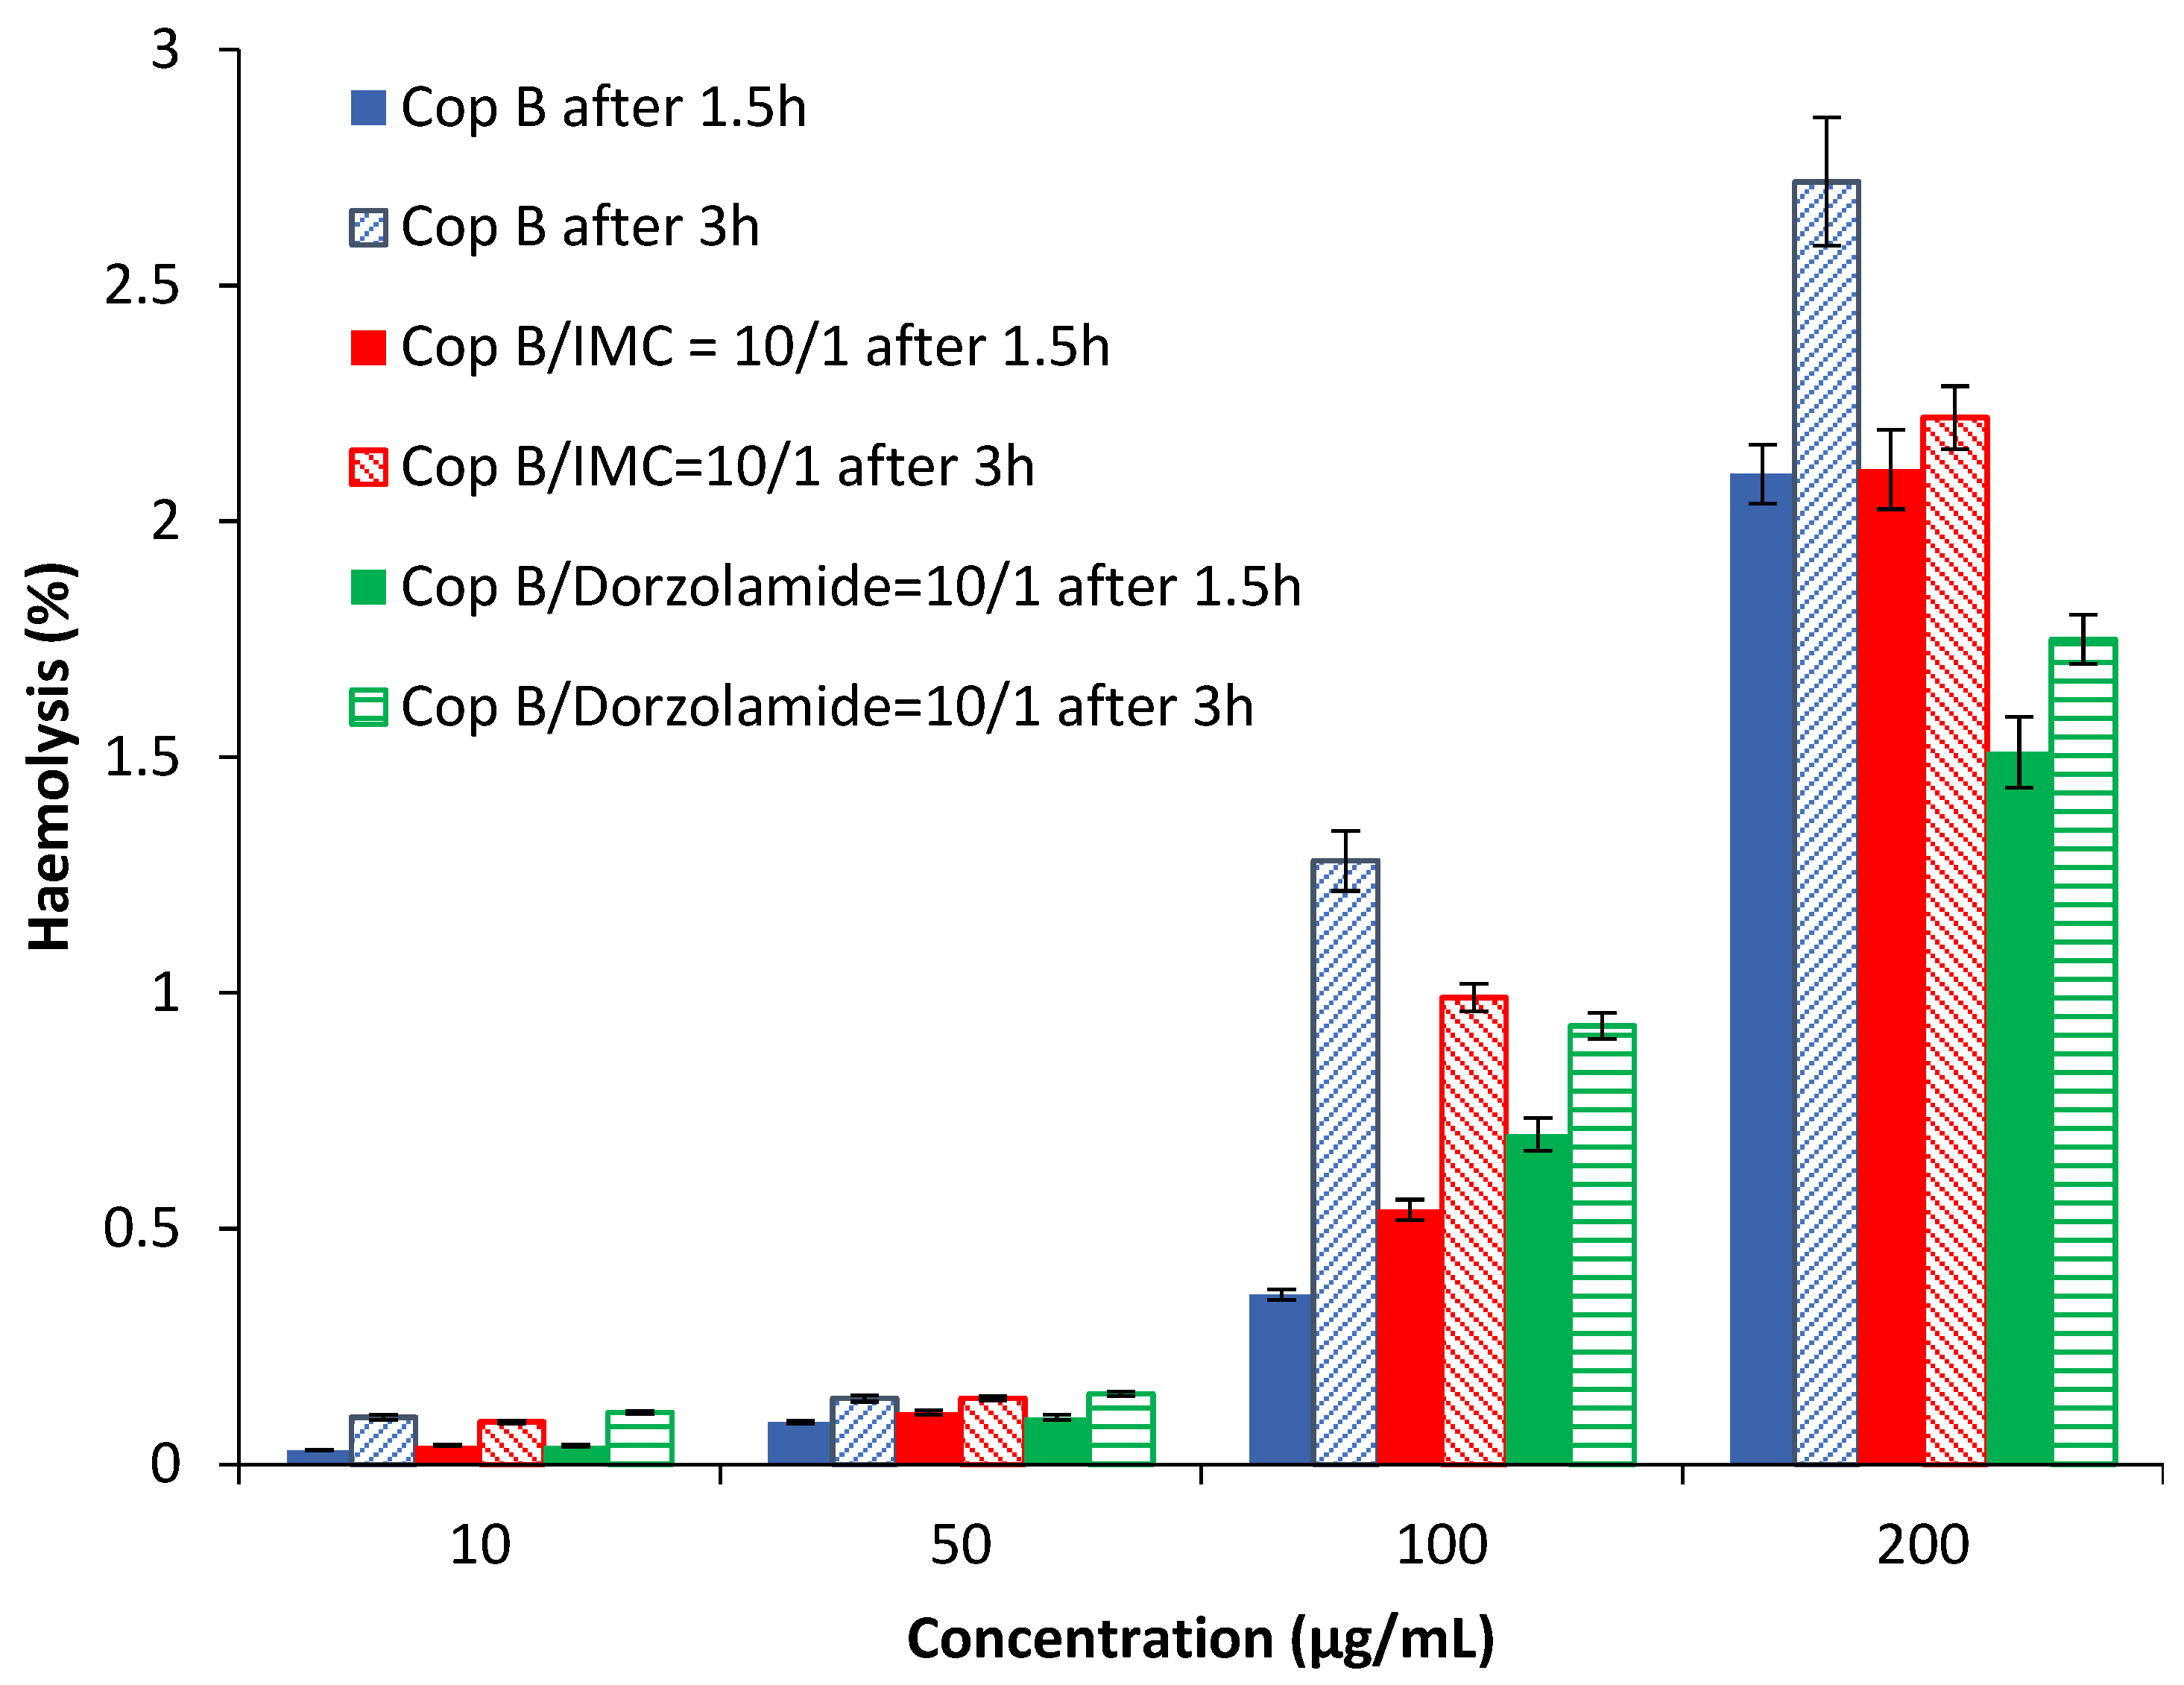

2.3. Assessment of the Haemolysis Degree